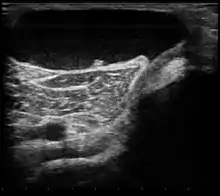

Ultrasound image of Baker's cyst | |

Diagnostic method | Confirmed by ultrasound or MRI[3] |

Diagnosis is by examination. A Baker's cyst is easier to see from behind with the patient standing with knees fully extended. It is most easily palpated (felt) with the knee partially flexed. Diagnosis is confirmed by ultrasonography, although if needed and there is no suspicion of a popliteal artery aneurysm then aspiration of synovial fluid from the cyst may be undertaken with care. An MRI image can reveal presence of a Baker's cyst.